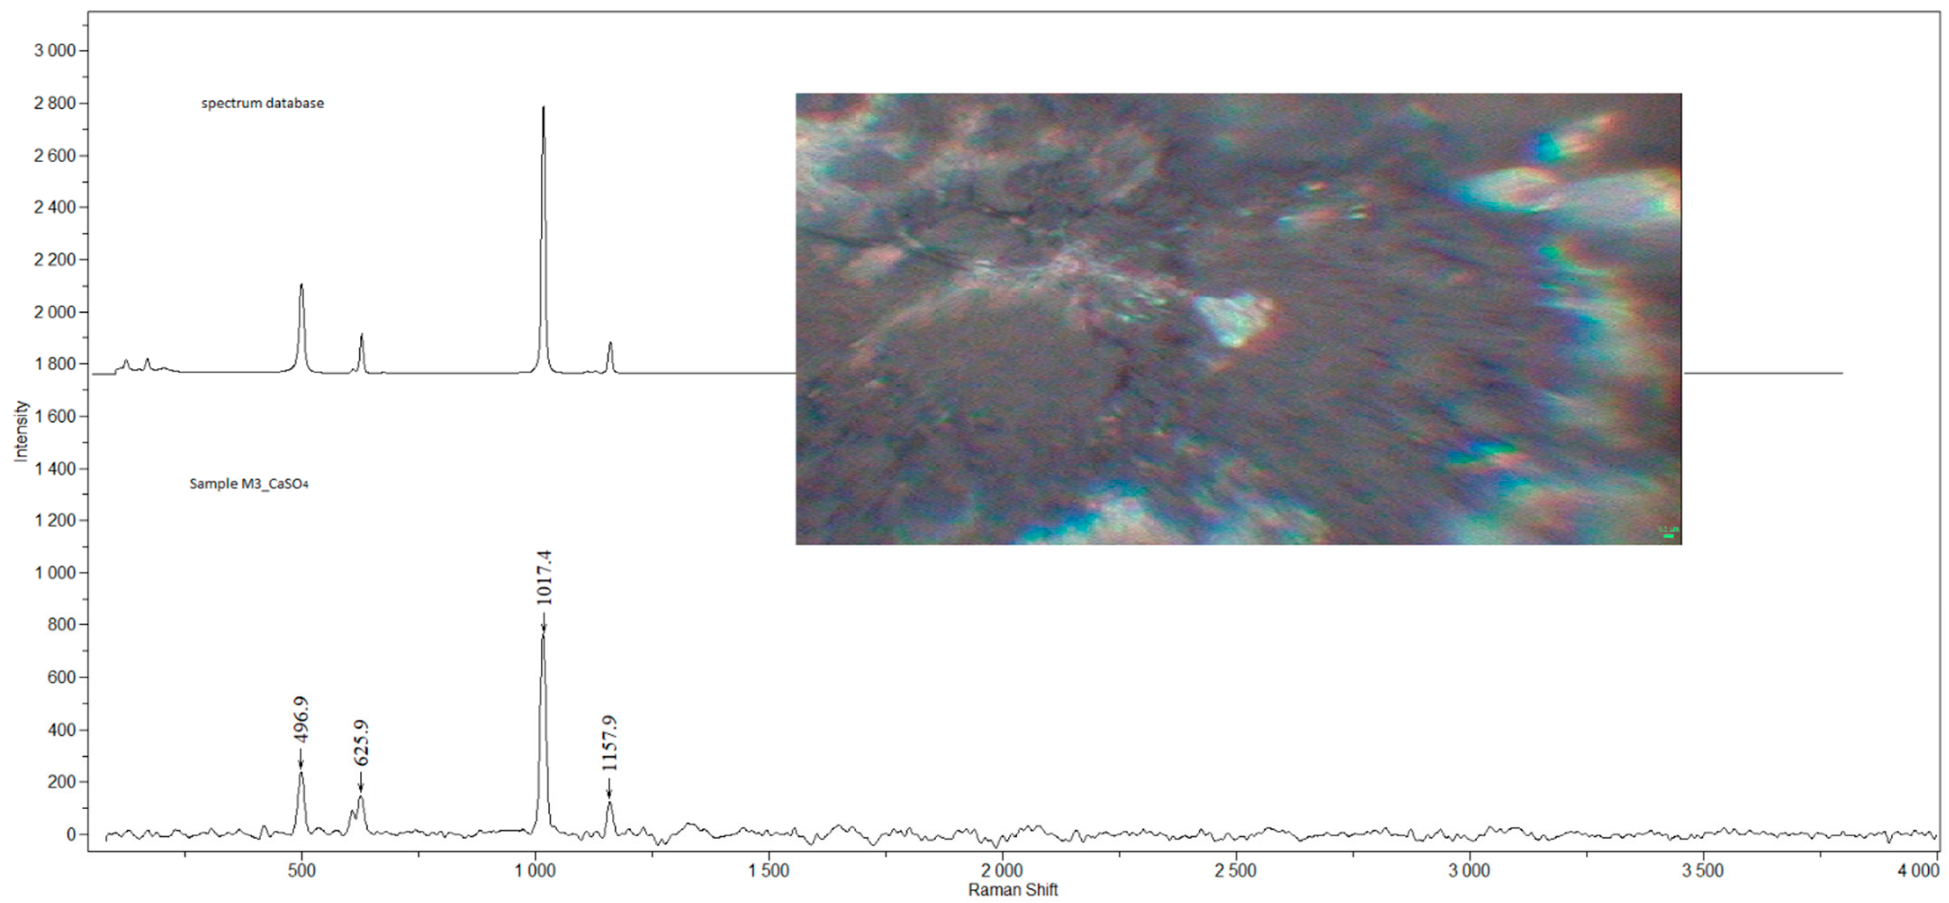

2.2. Raman Microspectroscopy

3.1. Detected Compounds

| M3 | m | 38 | N | welder (M) | AC, CaSO4, Fe3O4, GR, TiO2-A | 1 |